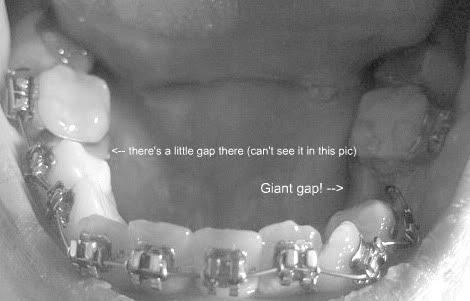

I got my braces on March 11, a week later. Getting the braces put on was an easy process. It got annoying to have my mouth open for so long but I tried to keep my mind off of it and daydream, haha. I got ceramic brackets on top and metal on the bottom. I currently only have the top wire in because I have to get a baby tooth pulled on the bottom before I can get the bottom wire put in. I'll be getting that done before my first adjustment so that at my first adjustment for the top teeth, I can get a bottom wire put in. I'm not looking forward to the tooth extraction but I can't wait to have a bottom wire put in so I can know that those teeth are on their way too.

I'm still working on being able to take pictures of the inside of my mouth but I tried... I have no idea if this is any sort of progress, or if it's just the way I held the camera that's making that one front tooth look like it moved a little. lol, I mean, it had only been one week since I got braces that I took the second photo so I wasn't really expecting to see a difference... but anyway, here are my top teeth.

Right after I got my top braces on, 3/11:

One week later, 3/18: